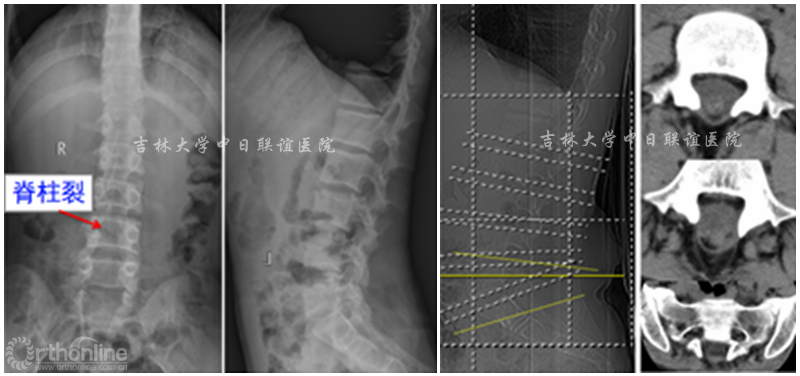

X线:L4—S5 脊柱裂。CT检查:L4-S5棘突及椎板缺失。腰椎MRI示:腰4-骶5椎板缺如,相应椎管内结构紊乱,脊髓末端与椎管内组织粘连固定于腰4椎体下缘,脊膜向外膨出,考虑脊柱裂伴脊膜膨出及脊髓栓系。

术前影像学检查: